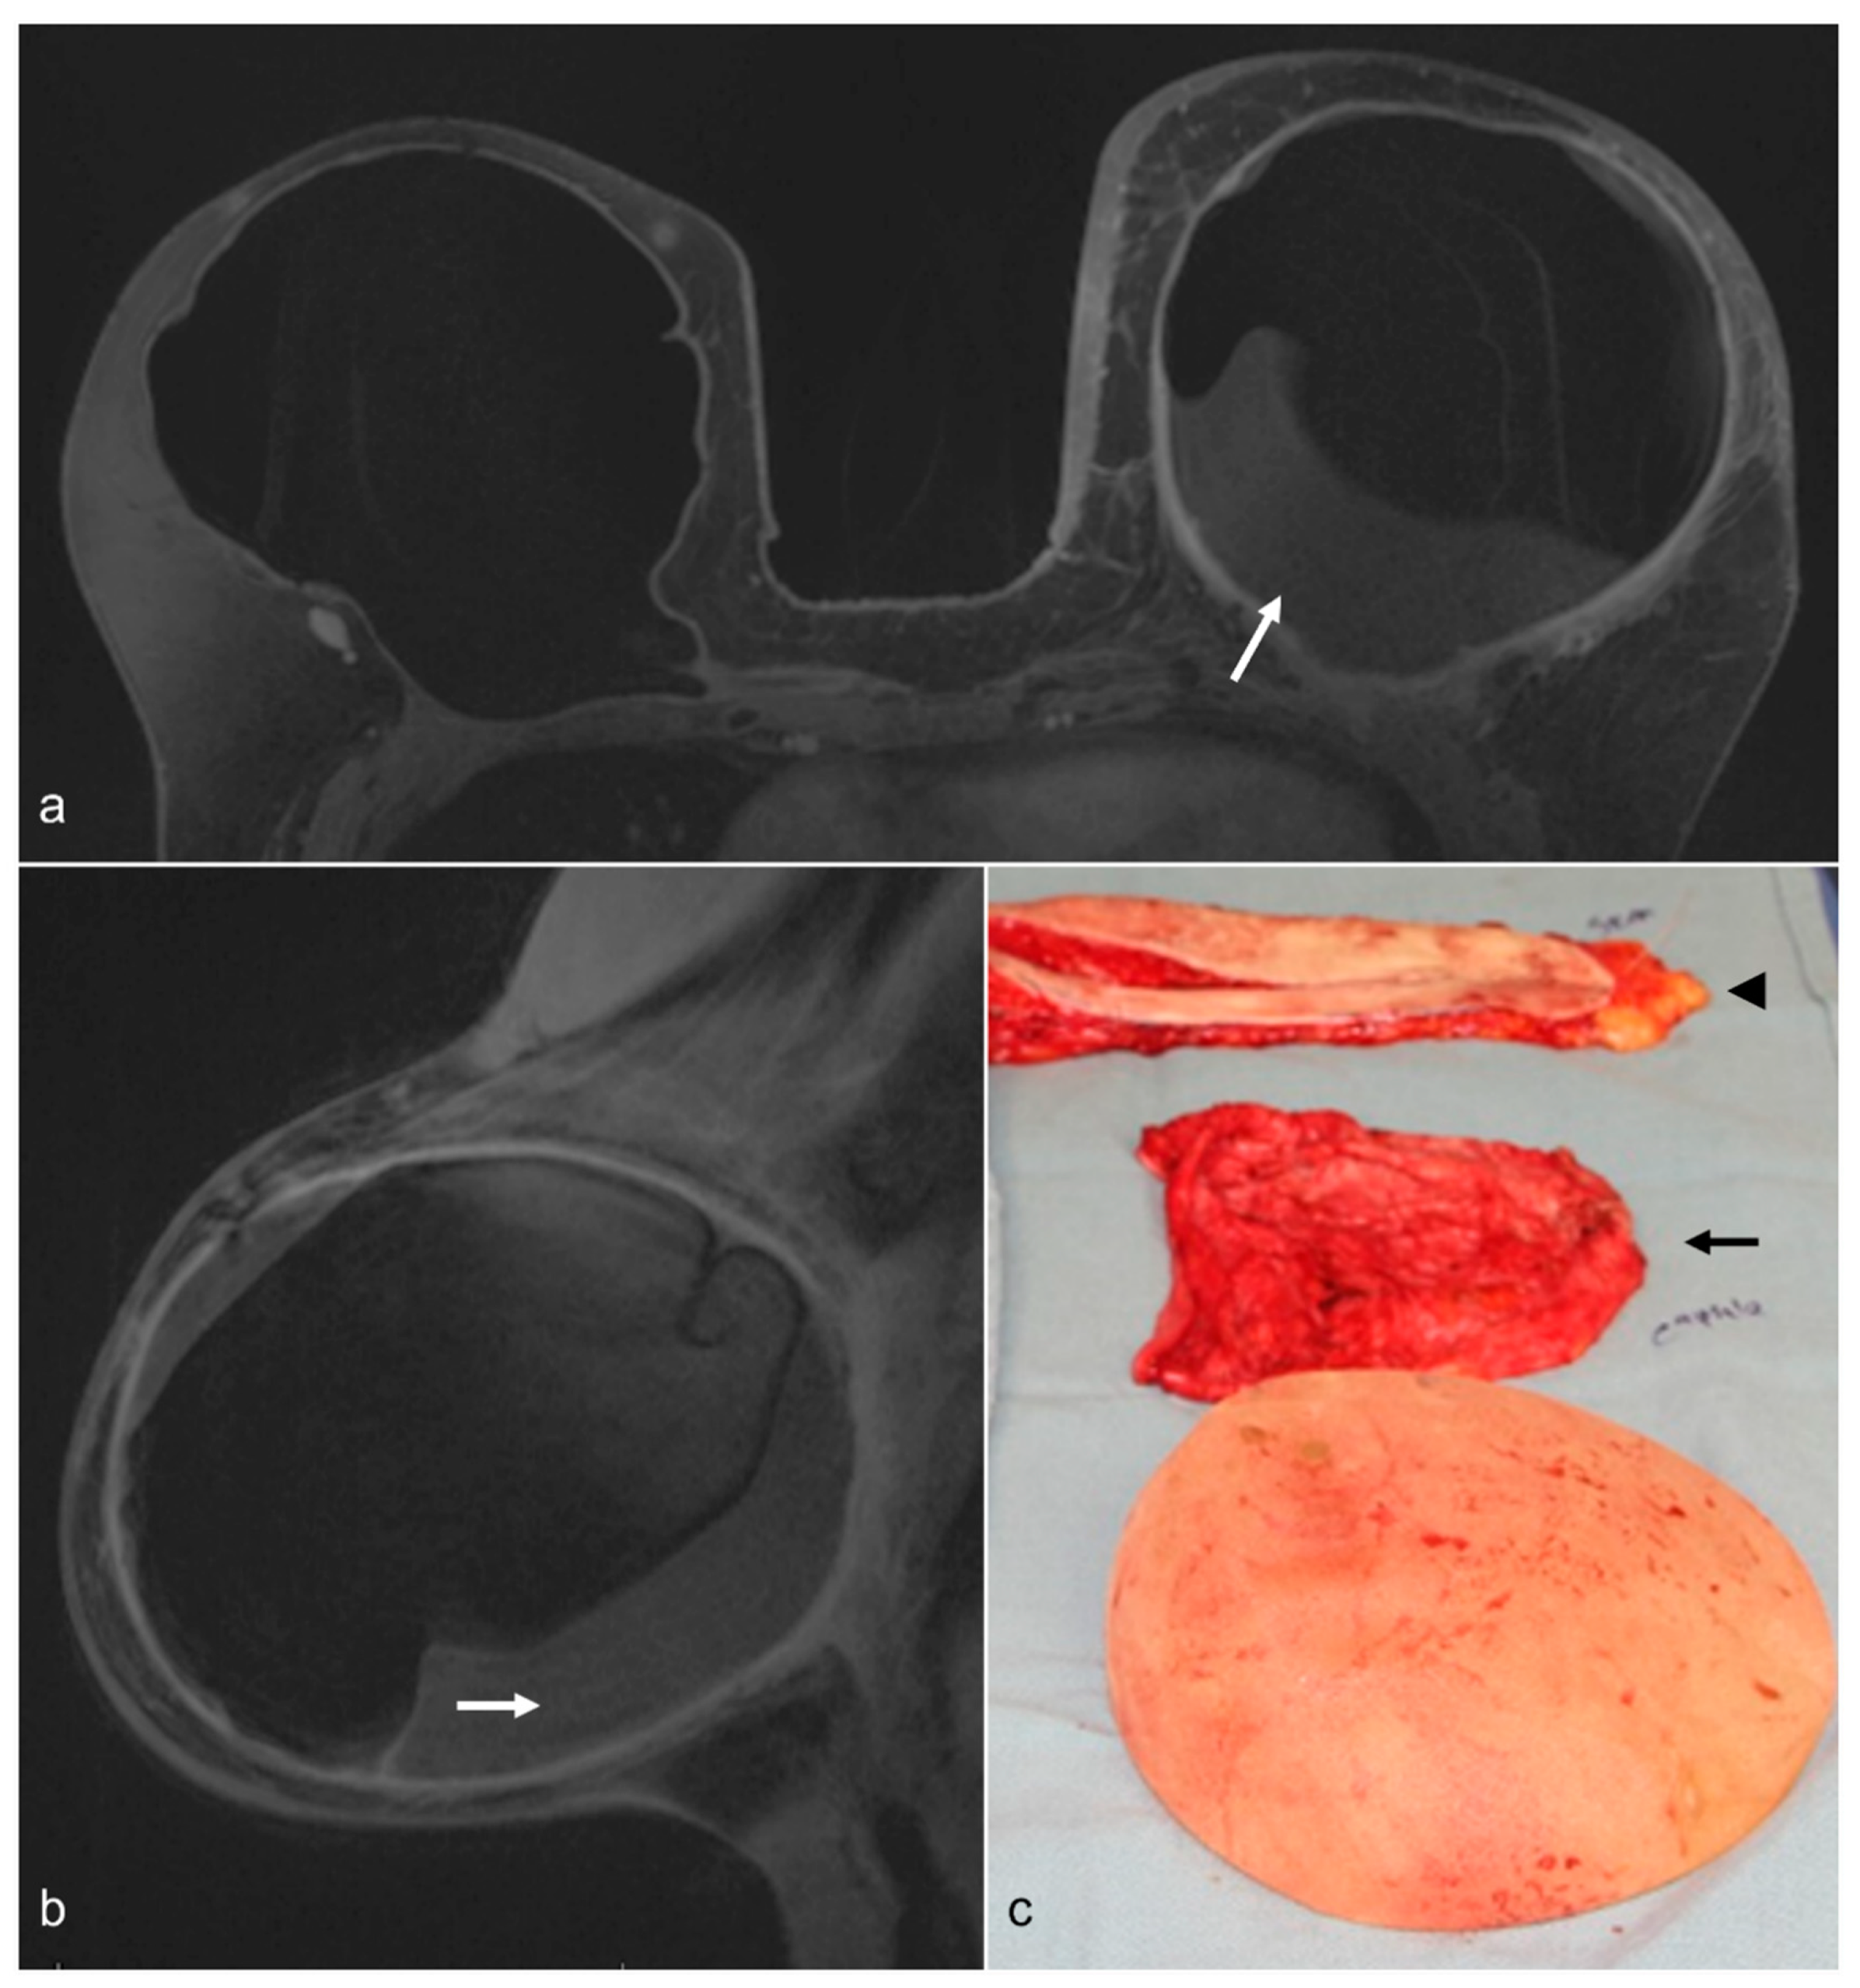

Figure 1. A 58-year-old woman with a history of bilateral prophylactic mastectomy and implant reconstruction. The patient had capsular contracture and a chronic fluid collection in the left breast (white arrows) on T1-weighted contrast-enhanced axial (a) and left sagittal (b) images. She underwent BES, and a photograph of the surgical specimen (c) shows the removed implant, the fibrous capsule (black arrow), and skin (arrowhead).